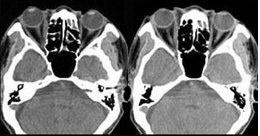

男,36岁,双眼球突出5月余,CT如图所示,应诊断为( )

A:眼型Graves病

B:肌炎型炎性假瘤

C:未见异常

D:眶内脑膜瘤

E:眶内淋巴瘤